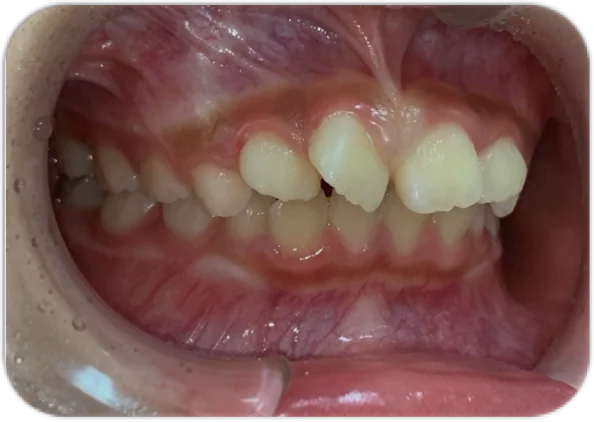

治療前

| 相談内容(主訴) | 前歯のガタガタが気になる |

|---|---|

| 診断結果/行った治療内容 | 叢生/アクティビティ+インビザライン矯正 |

| 治療期間/回数 | 1.5年/18回 |

| 治療費用 | 50万円(マイオブレイス+インビザライン)+アクティビティ 月一5,500円 |

| 治療のリスク/副作用 | 原則の装着時間を守らないと効果が出ません/まれに顎関節に症状が出ることがあります |